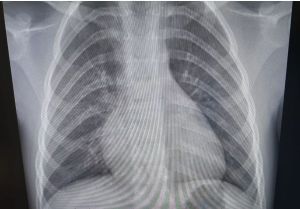

Слабый иммунитет и стресс могут привести к пневмонии

Пневмония является серьезным заболеванием легких, которое может развиться у людей с ослабленной иммунной системой.